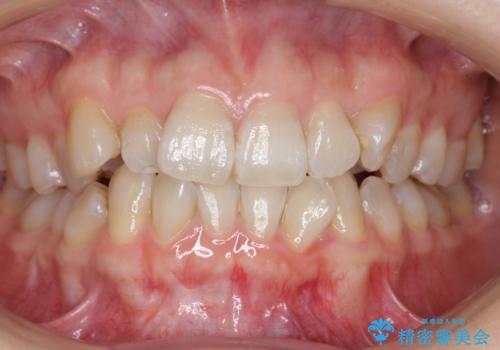

- 前歯のねじれを主訴に来院。

レントゲンを撮影したところ、右下4は神経のない歯で、外部吸収といって、根がだんだん短くなり、やがて抜けてしまう症状になっていました。また、アンキローシスを起こしている可能性があるため、動かない可能性が高い状態でした。

矯正治療で右下を抜歯し、スペースを天然の歯でつめる矯正治療を行いました。